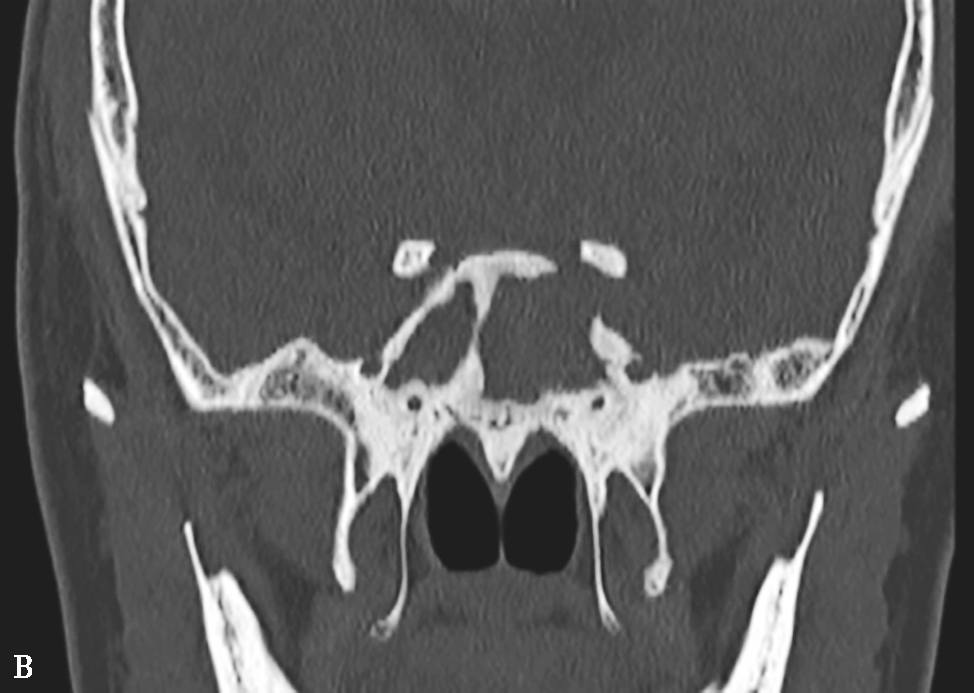

图1-3-26 鼻腔鼻窦肉芽肿性多血管炎

A、B.横断面CT及冠状面CT骨窗,示鼻背部塌陷,鼻中隔、双侧筛窦及上颌窦黏膜增厚,窦壁骨质增生硬化,内缘骨皮质欠光整;双侧中、下鼻甲形态欠自然,双侧眼眶内下壁骨皮质部分缺损,邻近内下象限肌锥外间隙可见弥漫性软组织增厚影,右侧为著;双侧上颌窦口-鼻道复合体增宽,钩突缺如;C.横断面T 1 WI,示双侧上颌窦腔可见略低信号,气-液平面可见,鼻背部塌陷,鼻中隔黏膜增厚,鼻咽顶后壁软组织增厚,呈等信号;D.横断面T 2 WI,示上颌窦腔病变呈高信号,余病变呈略低信号;E.横断面T 1 WI+FS+C,示窦腔、鼻中隔增厚,黏膜及其他受累结构呈中等强化,双侧翼腭窝及上颌窦后脂肪间隙受累,强化;F.冠状面T 1 WI+FS+C,示双侧眼眶内下象限肌锥外间隙病变呈中等强化,大脑纵裂及额部脑膜受累,呈弥漫性增厚强化